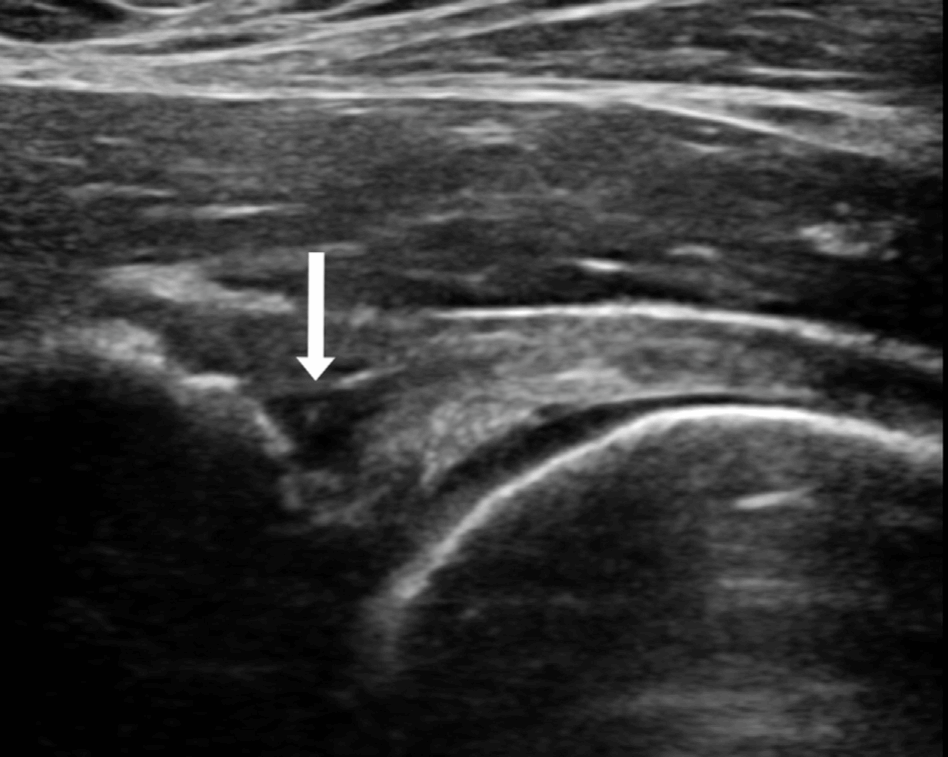

髋关节撞击综合征(FAI)的典型表现为腹股沟疼痛,但临床上亦不乏以髋后、腰骶和下肢等症状为主的非典型症状型FAI,这给临床诊断和治疗方式的选择带来了不小的挑战。为了解决这一问题,我科创新性地提出了超声引导下注射的方式用于诊断非典型症状型FAI。本研究共纳入了78名非典型症状型FAI患者,经过深入研究,我们发现超声引导下注射在诊断髋关节内病变的准确率高达91.7%,术后94.4%的患者临床结局评分超过了最小临床重要差异(MCID),91.7%的患者达到了可接受的症状状态(PASS)。基于上述研究结果,我们建议对于非典型症状型FAI的患者,可采用超声引导下注射的方式进行明确诊断。对于注射结果为阳性的患者,可考虑进一步采取手术治疗。这一诊断方法不仅提高了诊断的准确率,还为患者提供了更为精准的治疗方案。

Gao G, Fu Q, Wu R, Liu R, Cui L, Xu Y. Ultrasound and Ultrasound-Guided Hip Injection Have High Accuracy in the Diagnosis of Femoroacetabular Impingement With Atypical Symptoms. Arthroscopy. 2021 Jan;37(1):128-135.

超声引导下注射诊断非典型症状型FAI